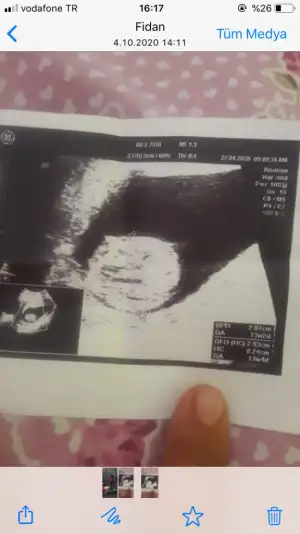

Erkek gibi sanki başka usgde paylaşınİkra Meyra, bana da bakar mısın? 12+5 burada

Erkekİkra Meyra, bana da bakar mısın? 12+5 burada

USG net değil başka varsa paylasinİkra cım bu da eltimin 14. Hafta da daha öğrenemedi yorum yaparmısın canım